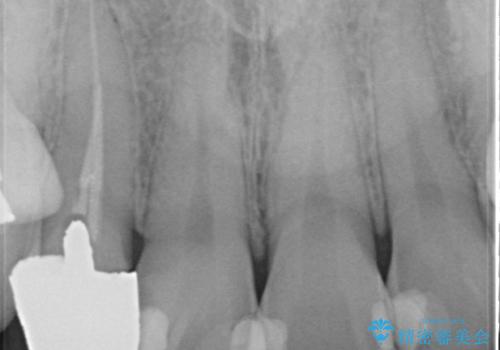

- 右上2番目の歯の被せ物と歯茎の間の継ぎ目が気になるといらっしゃった方の症例です。

再根管治療は希望されなかったため、クラウン除去後、オールセラミッククラウン(スペシャル)による補綴を行いました。